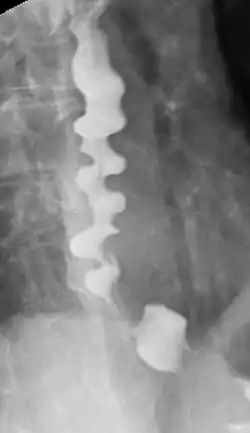

Breischluck-Darstellung des diffusen Ösophagus-Spasmus

Bei der Röntgendiagnostik kommt das Ösophagus-Breischluck-Verfahren zum Einsatz. Dabei schluckt der Patient ein Barium-haltiges Kontrastmittel, von dem während der Passage durch die Speiseröhre ein Röntgenbild erstellt wird. Auf diese Weise können Divertikel, Einengungen, die Längsausdehnung von Tumoren und der Ablauf des Schluckvorgangs (und damit auch Störungen und Reflux) sichtbar gemacht werden.[40]